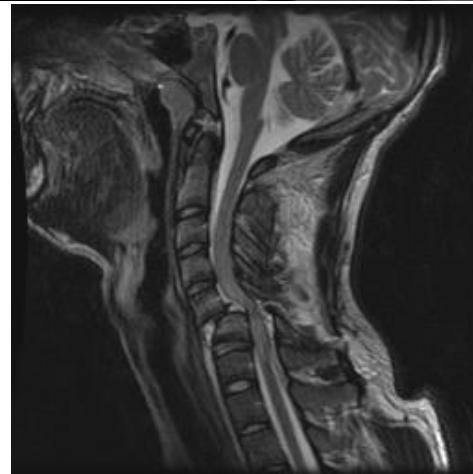

Cervical Spine Radiographs

Lateral View:

- All C-vertebrae & upper T1

- Prevertebral soft tissue width

- Four parallel curves:

- Front of vertebral bodies

- Back of vertebral bodies

- Posterior borders of lateral masses

- Bases of spinous processes

- Diagnosis: Confirmed with radiographs or CT scan

- MRI: Should be performed before surgery to identify associated disk herniation